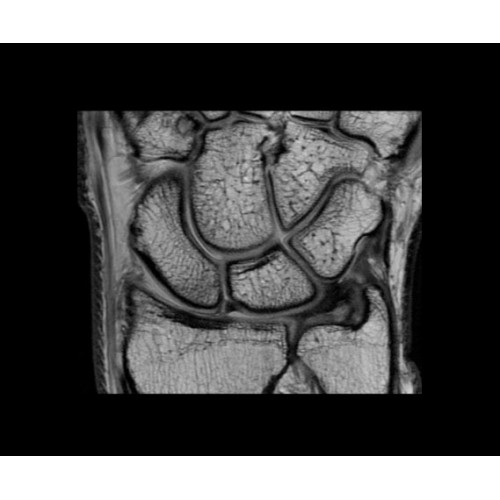

• NeuroWorks — универсальное решение для визуализации анатомии головного мозга, позвоночника, сосудов и периферических нервов с четкой дифференциацией тканей.

• OrthoWorks — программное решение для визуализации структур опорно-двигательного аппарата с прекрасным контрастированием тканей.

• 48-канальная катушка TDI для головы, входящая в базовую комплектацию SIGNA Architect, обеспечивает феноменальную производительность с учетом особенностей каждого пациента. Благодаря гибкому и универсальному дизайну, высокому соотношению сигнал/шум и передовым технологиям визуализации, таким как HyperWorks, учитываются потребности подавляющего большинства пациентов.